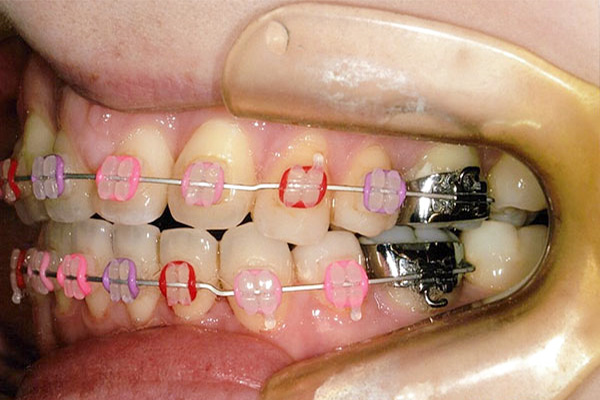

1年3ヶ月後